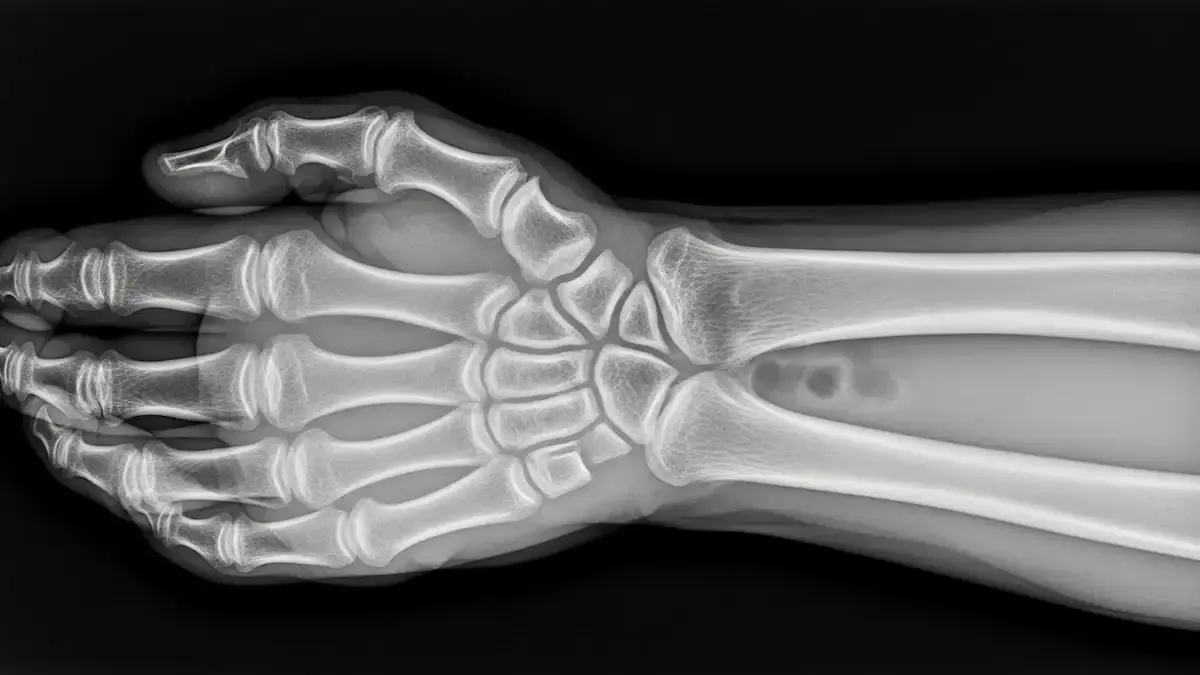

O diagnóstico precoce é deterninante, o que é corroborado por estudos brasileiros, como o publicado pela Sociedade Brasileira de Ortopedia e Traumatologia em 2023, que demonstram que aproximadamente 10-12% das fraturas do escafoide evoluem para pseudoartrose quando não tratadas adequadamente.

Este número alinha-se com pesquisas internacionais da Mayo Clinic, que reportam taxas similares de 5-15%.